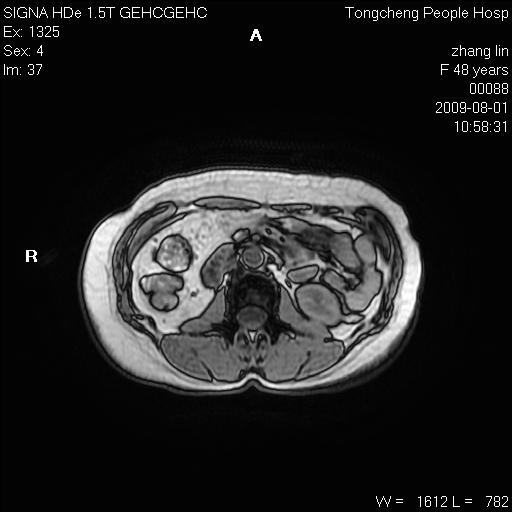

女,48岁。健康体检,彩超发现右肾占位性病变。平素健康。

临床诊断:右肾占位性病变,性质待定(囊肿?肿瘤?)。

上中腹部mr平扫+增强扫描,图像如下:

右肾上极见一类圆形病灶,t1wi呈等信号t2wi呈等高混杂信号,三期增强无强化,边界清---考虑囊肿出血。